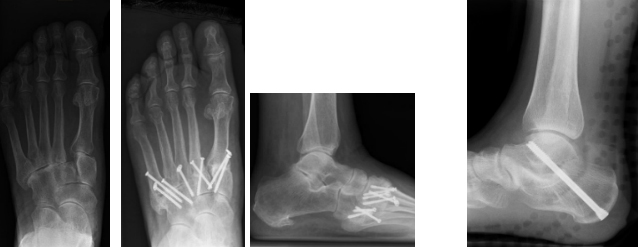

Das untere Sprunggelenk wird häufig gleichzeitig mit dem medialen (Double Arthrodese) und lateralen Chopartgelenk (Triple-Arthrodese) versteift und korrigiert. Aufgrund der komplexen Anatomie sollten allfällige Fehlstellungen immer mitkorrigiert werden. Geschieht dies unzureichend, wird eine Revisionsoperation notwendig. Dabei muß unbedingt die Fehlstellung korrigiert werden, gelegentlich sind auch hier Defektauffüllungen mit Knochenmaterial durchzuführen. Die Nachbehandlung erfolgt auf jeden Fall für 10-12 Wochen mittels Unterschenkelgipsen.

Werden sowohl das untere Sprunggelenks als auch das mediale und laterale Chopartgelenk in den pathologischen Prozeß miteinbezogen und müssen versteift werden, spricht man von einer Triplearthrodese. Dies ist häufig das Endresultat von Klumpfuß- bzw. Plattfußsituationen . Auch hier sind teilweise weitere Korrekturoperationen notwendig.

Auch im mittleren Fußbereich sind teilweise Versteifungen bei symptomatischen Abnützungen notwendig. Da sich in diesem Bereich die größte Krümmung der Fußwölbung befindet, ist auch in dieser Gelenksregion postoperativ die Nachbehandlung mittels Gips obligat.

Versteifung von Mittelfußgelenken